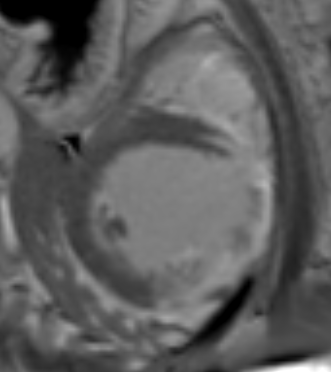

One month later the patient underwent cardiac MR imaging which showed the typical signs of pericardial agenesis: extreme levocardia of the heart resulting in elongation and ectasia of the aorta and pulmonary artery, interposition of lung tissue between the diaphragm and the base of the heart and increased cardiac mobility (‘swinging heart’). The late enhancement (LGE) revealed transmural scarring and hypo- and akinesia of the anterior wall.

Fig 2: MRI: transmural LGE of the anterior wall